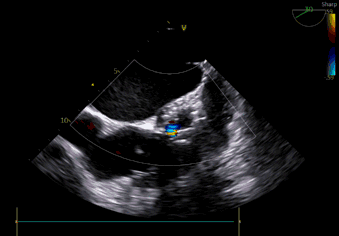

植入后瓣架深度

术中导丝跨瓣后20mm球囊预扩,超声判断冠脉风险尚可,植入L23 VenusA Plus可回收瓣膜位置良好,用23mm球囊后扩支架下缘,微少量瓣周漏。

术后即刻血压135/65mmHg,狭窄解除,释放后超声测量瓣下支架长度6mm标准位释放瓣膜位置完美。整台手术用时不足1.5小时,麻醉、超声等团队全程协作为手术顺利完成保驾护航。